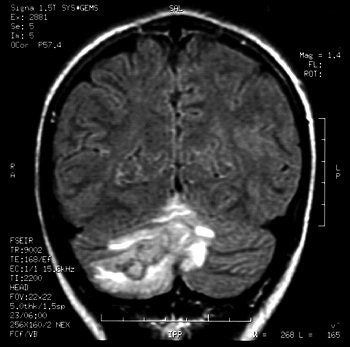

"As the popularity of body art grows, frequency and spectrum of piercing-site infections may increase. Physicians need to consider piercing sites as a source for potential distant infections," wrote Martinello and Cooney in an abstract for the 2001 Infectious Diseases Society of America conference. Images courtesy of Dr Richard Martinello.